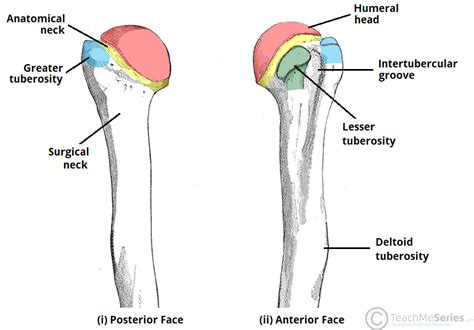

The medial epicondyle of the humerus is a bony projection located on the distal end of the humerus, which is the long bone of the upper arm. This anatomical structure plays a crucial role in the formation of the elbow joint and serves as an attachment point for several muscles and ligaments. The medial epicondyle is situated on the medial (inner) aspect of the humerus, opposite to the lateral epicondyle, and is a key landmark in the diagnosis and treatment of various elbow injuries and conditions.

From an anatomical perspective, the medial epicondyle is a rugged, triangular-shaped prominence that projects medially from the distal end of the humerus. It is the origin of the flexor muscles of the forearm, including the flexor carpi radialis, flexor carpi ulnaris, and flexor digitorum profundus. The medial epicondyle also serves as an attachment point for the ulnar collateral ligament, which provides stability to the elbow joint. The medial epicondyle is separated from the lateral epicondyle by a depression known as the cubital fossa, which contains several important neurovascular structures.